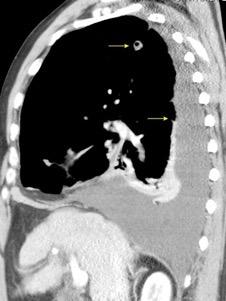

Tromboembolismo pulmonar.

Frecuencia del derrame:

Rx: 32%. TC: 47%

Unilateral. 85%

< 1/3 del hemitórax: 90%

Todos exudados

58% con eritrocitos

21% tabicación lo que causa demora en el diagnóstico

TEP. Empiema pleural. Atelectasia redonda

Porcel JM et al. Analysis of pleural effusions in acute pulmonary embolism: radiological and pleural fluid data from 230 patients. Respirology 2007/ Iguchi T et al. Desquamation of the subpleural lung parenchyma caused by empyema after pulmonary embolism: A case report. Respirol Case Rep. 2022 .